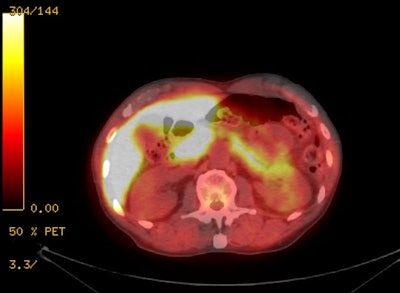

|

18F-Fluciclovine with

normal intense tracer activity in the liver, pancreas,

and urinary bladder. |